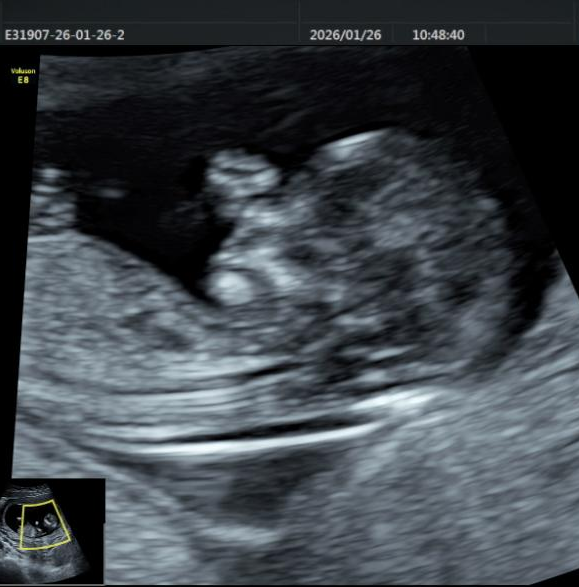

1、胎儿系统筛查

用超声之“窗”,细致探察宫内宝宝成长的每一个阶段,以专业守护新生。从孕早期的NT筛查,到孕中期的系统畸形排查,再到孕晚期的生长发育评估,超声医学科已构建起覆盖全孕周期的胎儿健康监测体系。